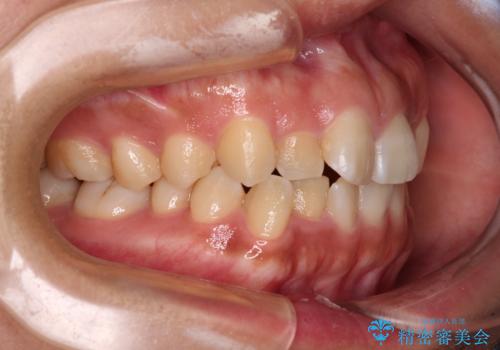

デコボコと捻れて前に飛び出した歯列 抜歯矯正でスッキリした口元に

- 前歯のデコボコと口元の突出感を気にして来院された患者様です。

非抜歯矯正ではデコボコを解消することでより口元が突出してしまうため、上下左右の小臼歯4本の抜歯を行い、ワイヤー装置による矯正治療を行うこととしました。

上顎小臼歯の歯根が左右ともに大きく曲がっており、スペースクローズに時間がかかってしまいました。